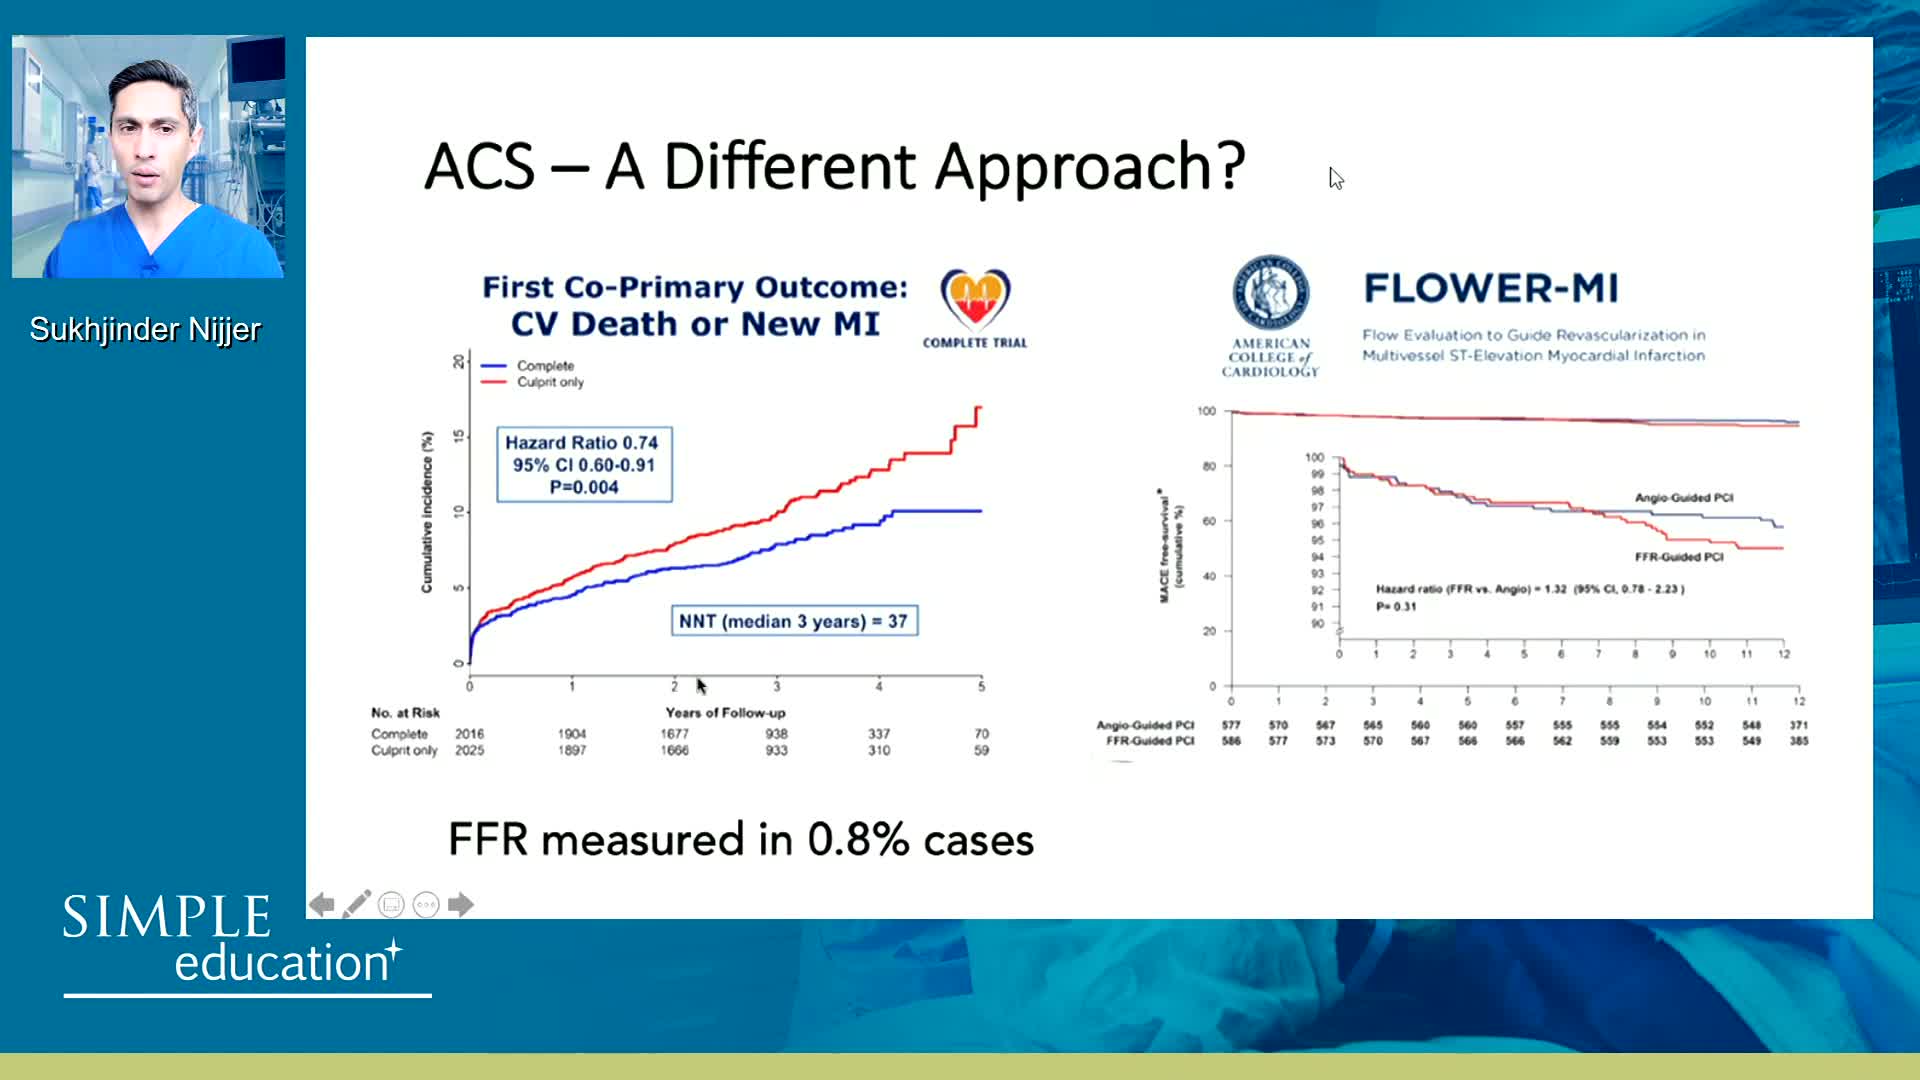

Spotlight Discussion: Management of multivessel disease in patients with acute coronary syndromes

Intracoronary guidance in acute coronary syndromes - Dr Hernan Mejia-Renteria